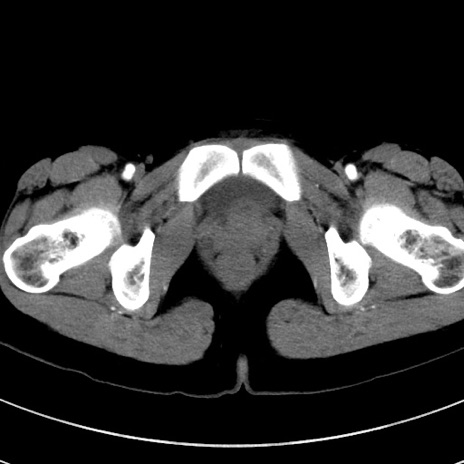

症例17(横断像)

【症例】20歳代女性

【主訴】嘔吐、下腹部痛

【現病歴】昨日夕食後に嘔吐し下腹部痛が出現。本日になっても嘔吐持続し改善しないため来院。

【身体所見】意識清明、BT 37.2℃、BP 108/67mmHg、腹部:平坦、やや硬、下腹部正中から右にかけて圧痛あり、反跳痛軽度あり、tapping pain(+)。

【データ】WBC 13600、CRP 14.94